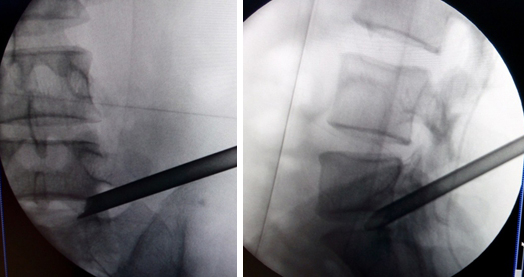

(图)穿刺针定位

(图)置入扩张管